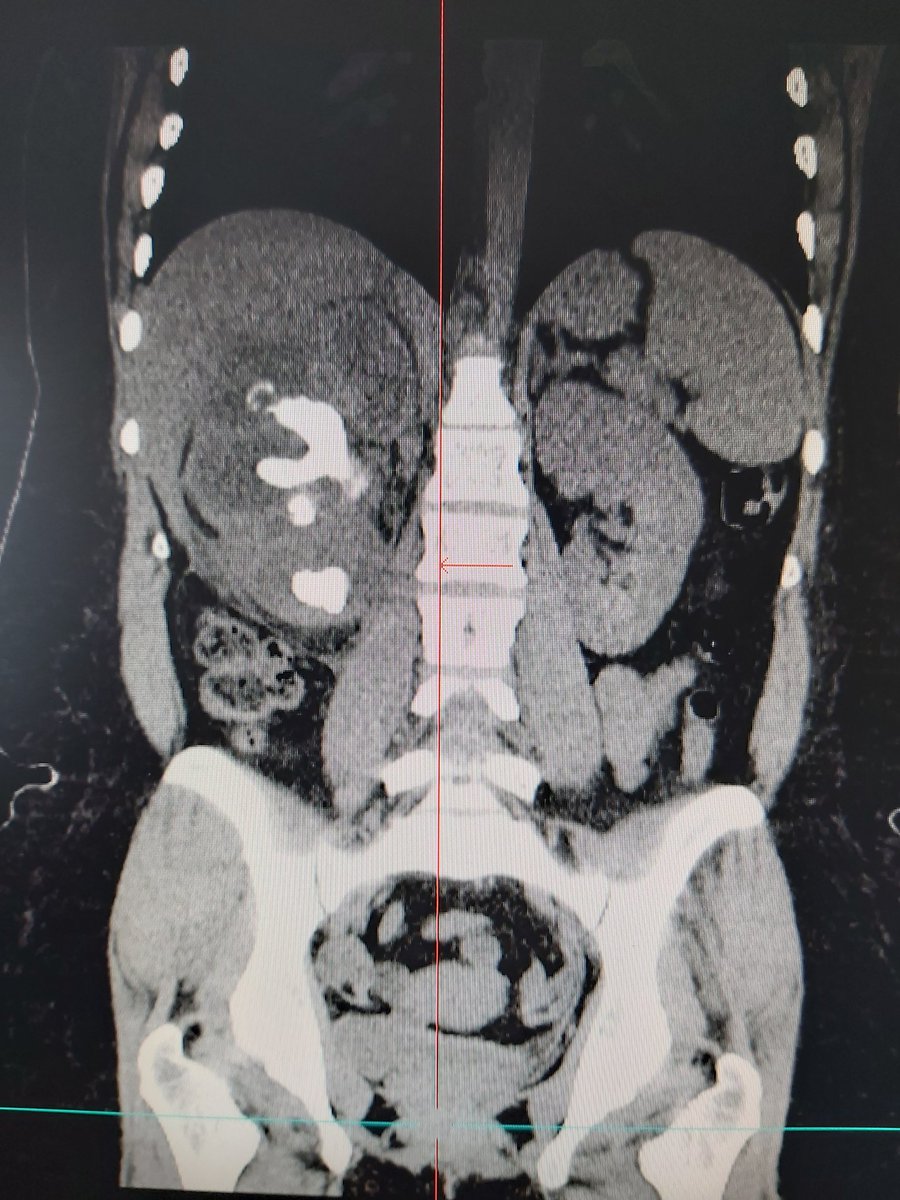

Second

#XGP in a month... important to establish prevention measures from the first level of medical care to avoid such cases.@jonaSalas69@rendon_ocampo#UroSoMepic.twitter.com/NDQG1Cbmnn